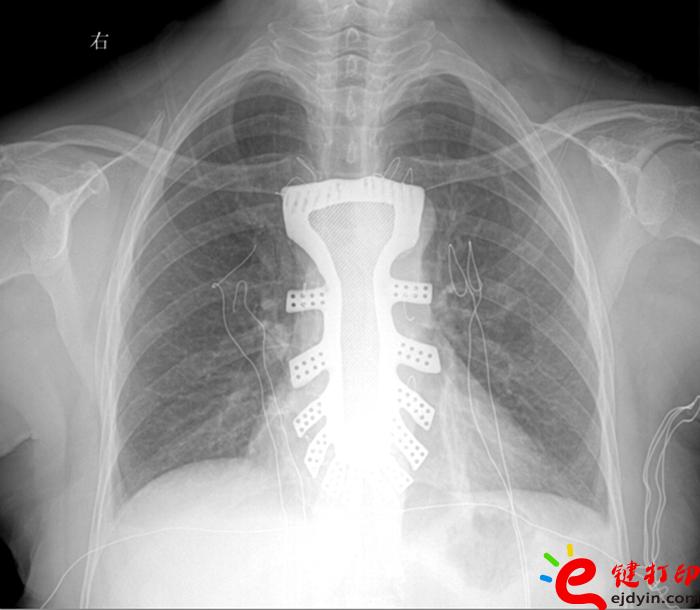

當然,“3D打印”的世界遠不止如此。據(jù)參加大會的專家和企業(yè)負責(zé)人介紹,目前“3D打印”已被運用在文化創(chuàng)意、文物修復(fù)、生物醫(yī)療、工業(yè)設(shè)計等多個領(lǐng)域。如,在航空航天器材上,一些關(guān)鍵零部件采用“3D打印”一次成型,使得其功能更加實用,重量大幅減少;在醫(yī)療領(lǐng)域,“3D打印”被運用于牙齒再造和骨骼修復(fù)等方面,從而使治療更加精準。